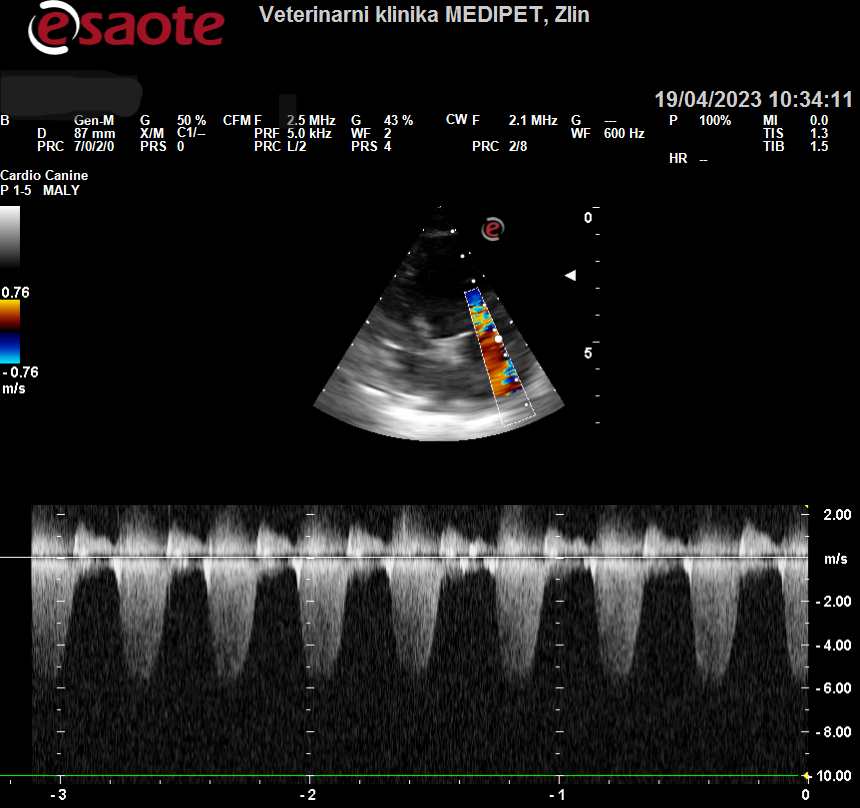

Prvním krokem je vždy přesná diagnóza.  Mezi nejčastější onemocnění, se kterým se u zvířecích pacientů setkáváme patří myxomatózní degenerace mitrální chlopně u menších psů, dilatační kardiomyopatie u větších plemen a hypertrofická kardiomyopatie u koček. Na základě klinického vyšetření a kardiologického vyšetření zjistíme v jaké   fázi se onemocnění nachází a podle toho sestavíme individuální plán léčby, který zahrnuje pravidelné podávání léků a pravidelný monitoring.

Mytomatózní degenerace mitrální chlopně-spektrální doppler.